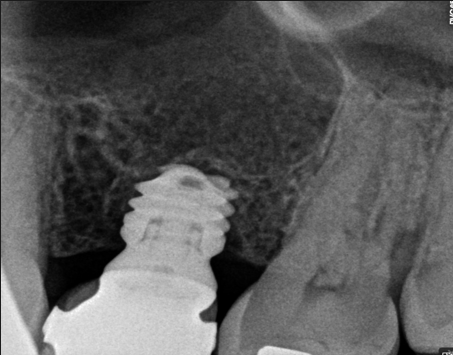

Los implantes cortos son fijaciones de menor longitud que los implantes tradicionales. Están diseñados para colocarse en zonas donde el hueso maxilar o mandibular se encuentra muy reducido, evitando así cirugías adicionales de regeneración ósea. A pesar de su menor tamaño, ofrecen una gran estabilidad y

permiten rehabilitar áreas comprometidas de forma predecible.